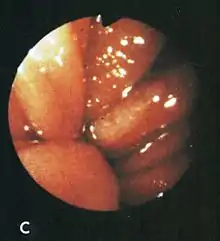

Cameron lesions. A long linear erosion and smaller non-linear erosions on the crests of inflamed gastric folds at the level of the diaphragm.

Based on their surgical observations, Windsor and Collis in 1967[4] proposed that blood loss was due to local trauma to the stomach where it rides to and fro in the hiatus on respiration. Boutelier et al.[8] noted on gastroscopy ulcers and erosions at the level of the neck of the hernia in individuals with acute and chronic bleeding, but no detailed description was given. Cameron and Higgins in 1986[1] described linear gastric erosions, later called "Cameron lesions", in people with x-rays showing one-third or more of the stomach above the diaphragm.[9][10][11][12][13][14][15] (figure 1). Over 6 years, Cameron and Higgins studied 109 persons with large hiatal hernias, 55 with anemia and 54 without anemia, at esophagogastroduodenoscopy. Cameron lesions, often multiple, were found at or near the level where the herniated stomach was constricted by the diaphragm. The lesions were typically white, superficial, linear, and oriented along the crests of inflamed appearing mucosal folds (figure 2). Small amounts of blood were often seen on the lesions (Fig 3). Mucosal folds at the diaphragm level were often seen rubbing against each other on respiration (Fig 4). It was proposed that the lesions were caused by mechanical trauma at the level of constriction by the diaphragm [1] Cameron lesions were found in 42% of persons with anemia compared to 24% in those without anemia, a statistically significant difference, p<0.05. Spots of fresh or clotted blood were seen on the lesions in 25% of persons with anemia compared to 7% without anemia, also a significant difference, p<0.05. In the 109 persons in this study, 15 had reflux esophagitis, 11 had peptic ulcers, and 7 had Barrett's esophagus, but none of these findings correlated with anemia. Thus, in people with large hernias, Cameron lesions with evidence of slow bleeding were associated with iron deficiency anemia.